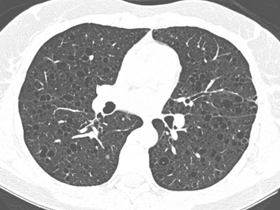

Imagens associadas à LAM e à esclerose tuberosa

Pulmão com múltiplos cistos

Tomografia de tórax cistos difusos pelo pulmao